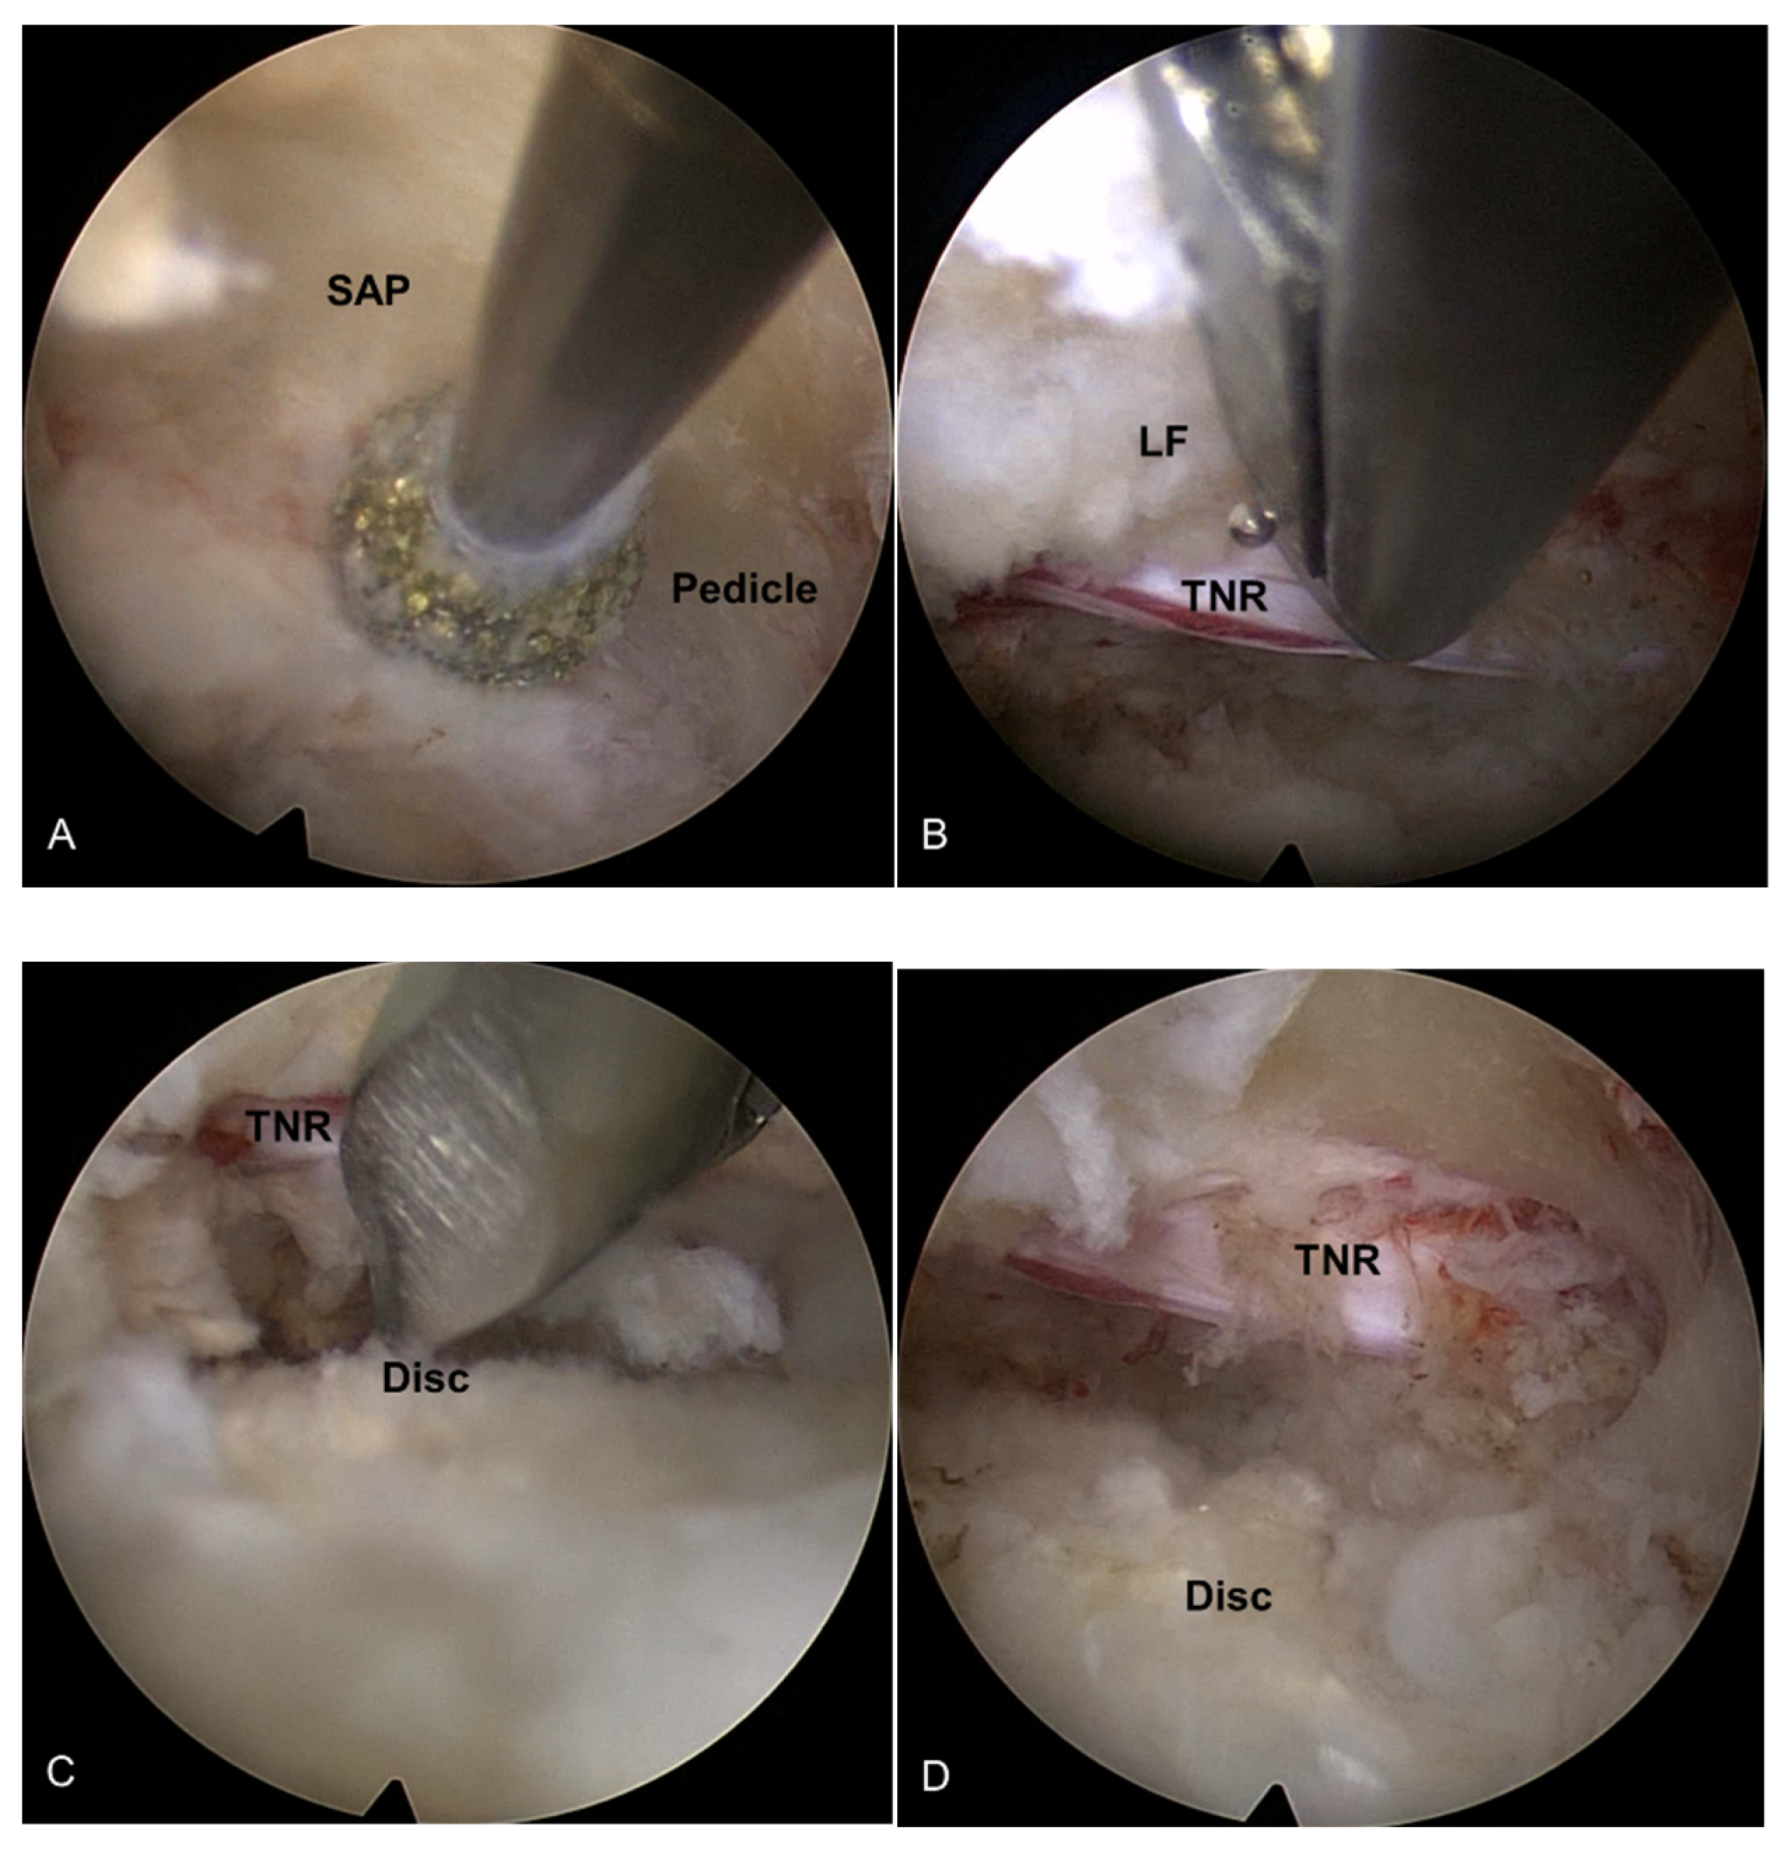

Figure 2.

Intraoperative endoscopic pictures TELLRD. (A) Bony unroofing using endoscopic burrs and punches. The hypertrophic SAP and part of the pedicle were undercut using an endoscopic burr (L4–L5, left). (B) Ventral decompression with removal of thickened LF using endoscopic punches. (C) Dorsal decompression with removal of redundant disc and shoulder osteophytes using endoscopic burrs and punches. (D) Final endoscopic view showing the released TNR. TELLRD, transforaminal endoscopic lumbar lateral recess decompression; SAP, superior articular process; LF, ligamentum flavum; TNR, traversing nerve root.

2.2.2. Endoscopic Bone Work

The early step of the lateral recess decompression focused on resecting the hypertrophic SAP with continuing pedicle and the medially-located inferior articular process (IAP) that compresses the traversing nerve root. The initial endoscopic view included the disc and the lateral surface of the SAP. Specific endoscopic burrs and micropunches were used for precise bone resection. Various types of burrs were applied for sufficient bone resection; round or side-cutting, straight or articulating, spanning between the upper and lower pedicle margins. The lateral and ventral portions of the hypertrophic SAP and IAP were systemically undercut from pedicle to pedicle and from lateral to the medial pedicular line until the ligamentum flavum (LF) was sufficiently exposed. During this process, a part of the pedicle was also resected until the epidural space with the traversing nerve root (TNR) was clearly defined. This point can be the typical landmark of the lateral aspect of the spinal canal. After confirming the TNR behind the pedicle, the exposed LF was performed. The lateral bone window was made large enough to facilitate subsequent soft tissue decompression. Bleedings from the bone surface and epidural space were controlled using a steerable radiofrequency (RF) coagulator tip and hemostatic agents (Figure 2B).

2.2.3. Endoscopic Soft Tissue Decompression

After adequate lateral bony unroofing and widening, soft tissues, such as thickened LF, redundant disc, and shoulder osteophyte, were removed to alleviate compression on the TNR. Dorsolateral decompression was initiated by removing the hypertrophic LF with micropunches, small Kerrison punches, and semiflexible forceps with steerable RF coagulator tips. As the LF was gradually removed, the TNR and dural sac were also exposed. The decompression process required delicate tissue dissection under endoscopic visualization, and hydrostatic irrigation pressure was employed to aid dissection between the LF and neural tissues. The TNR was released from the axillary portion to the level of the inferior pedicle (Figure 2B). After sufficient dorsal decompression, a ventral decompression was performed. The shoulder osteophytes and redundant discs were removed using micropunches and burrs. The working sheath and endoscope were further advanced into the epidural space ventral to the dural sac. As the decompression progressed, the TNR became exposed and released (Figure 2C). This ventral work can be gradually performed from the lateral side to the midline, even to the contralateral side, as required. At this point, the surgeon can also encounter epidural or bone bleeding that interferes with the surgical field, which should be controlled using RF and hemostatic agents.

2.2.4. The Target Point of the Decompression

The endpoint of TELLRD was determined by identifying the released TNR with the dural sac from the axillary to the inferior pedicle level. Successful neural decompression was confirmed by observing the strong pulsation of the nerve in synchronization with the patient’s heartbeat and soft mobilization upon probing (Figure 2D). After adequate hemostasis, a sterile dressing was applied with a one-point subcutaneous suture. The patient was monitored for at least three hours to detect any adverse events and then discharged within 24 h. When required, postoperative imaging studies were conducted for precise pathological assessment (Figure 3).